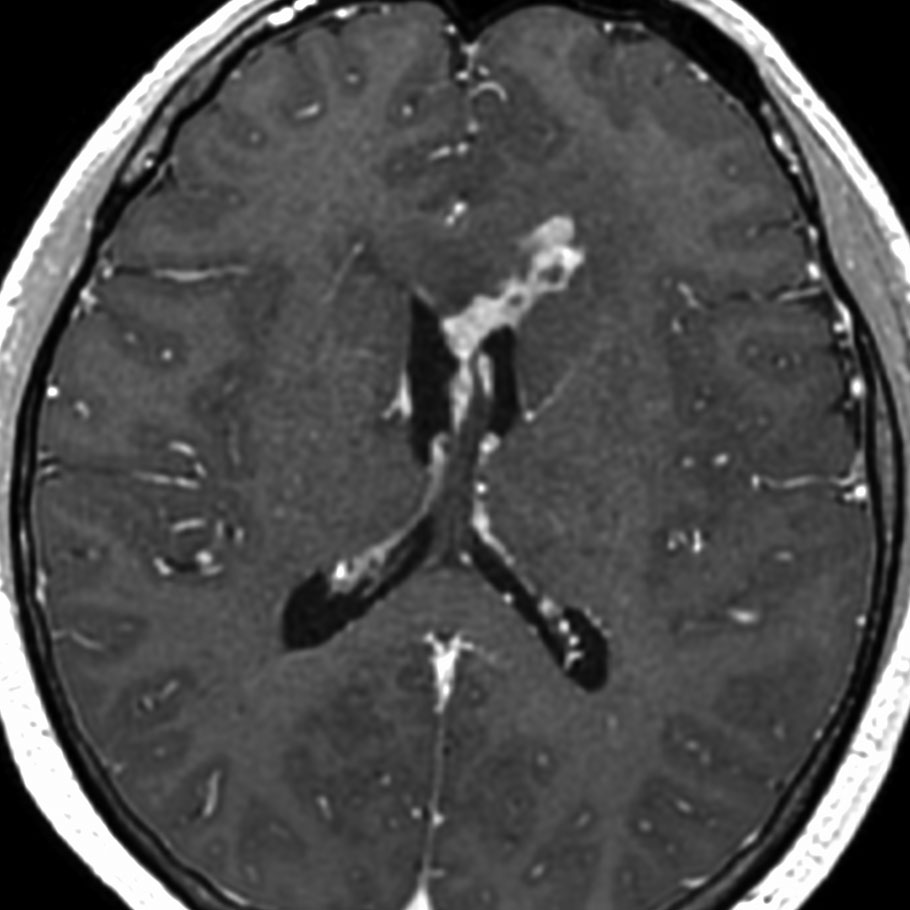

ガドリニウム増強では,前頭葉腫瘍というより,側脳室壁にベトベトくっついているような腫瘍です。germinoma特有のsubependymal infiltration像を示します。

生検後2ヶ月,セカンドオピニオンのために受診された時の画像です。腫瘍が縮小傾向にあります。入院中に行われた何度かのCT被曝の影響で,germinomaの退縮が生じたのだと判断しました。